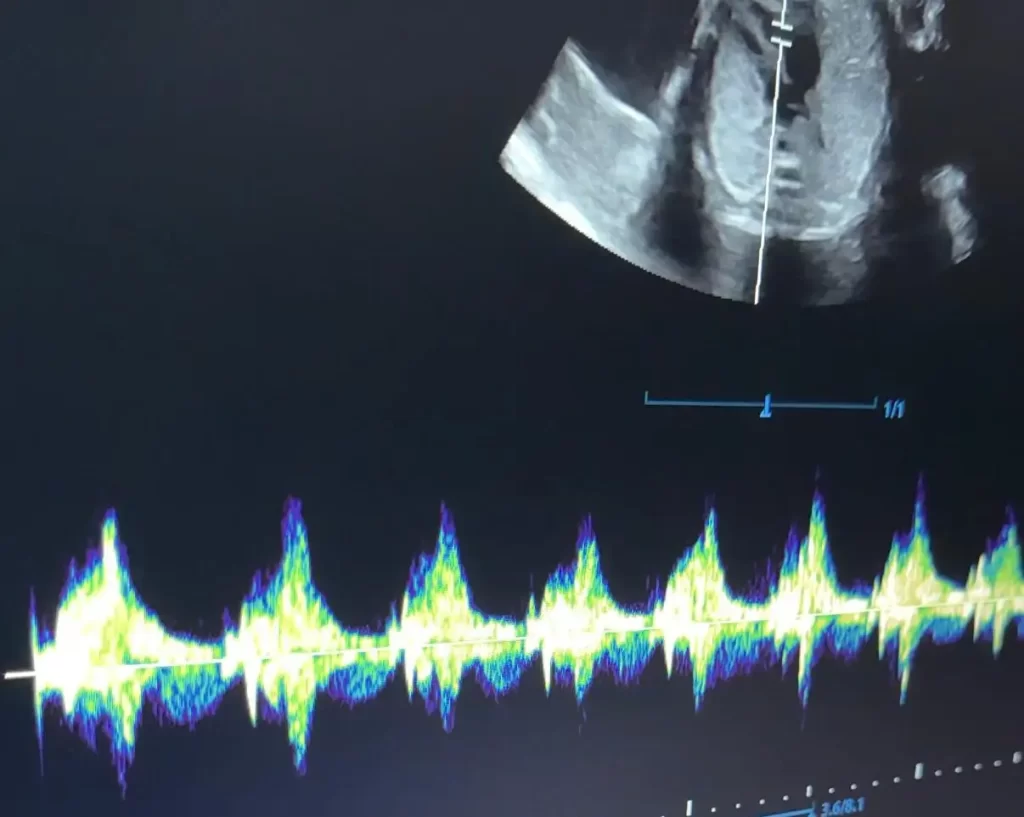

HearDBaby

11-42 weeks

Feel the joy of connection by hearing your baby’s heartbeat at any time during your pregnancy.

- Early Peek (8–14 weeks) – See baby’s movements and heartbeat